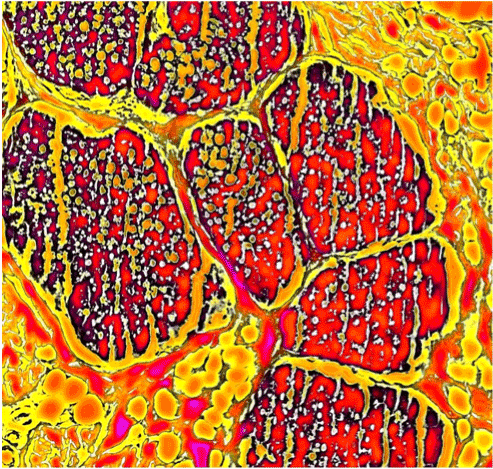

The view in the microscope is part of pathologists’ and medical technical assistants’ daily routine. For many of them it’s almost a passion. Are you sometimes fascinated by the beauty of the slides that you see under the microscope, or are you too much focused on finding a diagnosis? Every now and then there are very striking patterns, and sometimes there are associations: a heart, an animal, a flame. Even ordinary structures such as hair, glands, or vessels can "look good". Do you still notice that fact after years of looking through millions of slides under the microscope? Can you see “art” in histological slides? That’s what Anne Kerber thinks; she has been working as a medical technical assistant in the field of Dermatopathology for almost a quarter of a century. For her “Histological POP ART project”, 3-5 millimeter slides were made from normal or diseased skin, and then they were stained with H&E and

Mallory’s trichrome. Microscopic examination revealed special looking structures that seem to be “photogenic”. Pictures were taken by a microscope camera and were changed into “Pop Art” pictures by using different computer programs. The exact process is a little secret. It takes some time to find the best-looking color composites. Also, the size of the single colour fields and the sharpness of several areas have to be determined. The result of this experimental work is a “Pop Art style” histological picture. At this point, even normal skin structures like hair and glands show an extraordinary design. There is no contradiction between morphology and art. Quite the contrary, there is an old saying that art, or beauty, is in the eye of the beholder. This is especially true for medical lay persons - even they love these histological Pop Art pictures. Please follow us on a little journey through the skin and discover its unique beauty.

Figure 2. Pop Art style